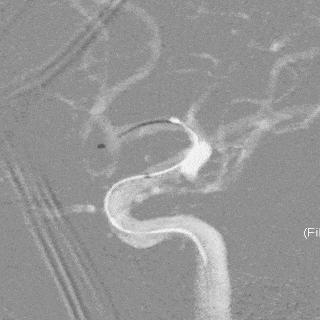

术前影像

栓塞过程

先通过微导管填塞成篮圈,输送支架到左侧大脑中动脉下干并释放,使支架覆盖动脉瘤开口。依次填入Jasper®SS弹簧圈多枚。

术后即刻影像